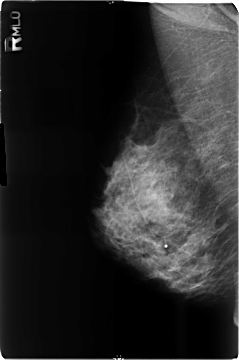

B_3509_1.RIGHT_MLO

RIGHT_MLO LINES 4680 PIXELS_PER_LINE 3104 BITS_PER_PIXEL 12 RESOLUTION 50 NON_OVERLAY

FILE: B_3509_1.LEFT_MLO.OVERLAY

TOTAL_ABNORMALITIES 3

ABNORMALITY 1

LESION_TYPE CALCIFICATION TYPE PLEOMORPHIC-FINE_LINEAR_BRANCHING DISTRIBUTION CLUSTERED

ASSESSMENT 4

SUBTLETY 3

PATHOLOGY MALIGNANT

TOTAL_OUTLINES 1

BOUNDARY

ABNORMALITY 2

ABNORMALITY 3